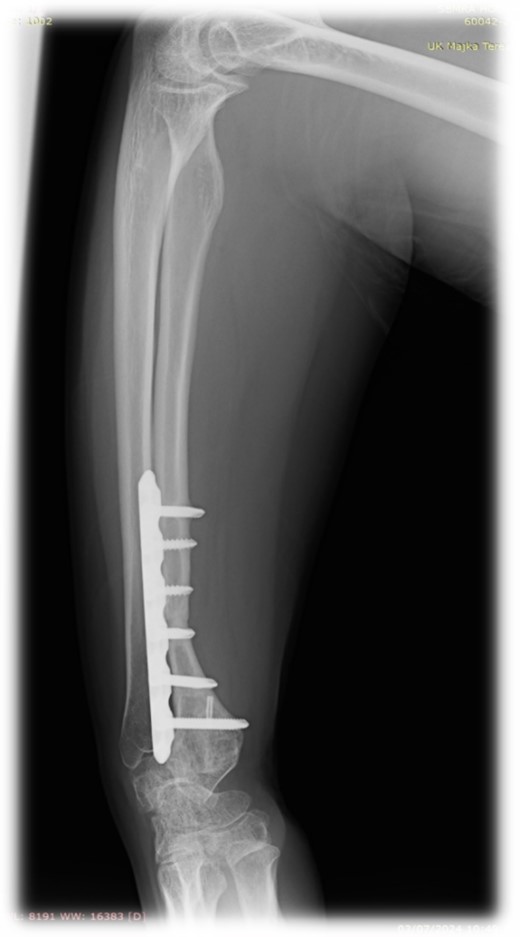

At 2 years follow-up, no clinical and X-ray signs of tumor recurrence or graft resorption were detected, both X-ray and CT confirmed that bone healing has been achieved (Figs 7 and 8) On physical examination, the patient has decreased wrist dorsal and palmar flexion, all other wrist movements are in normal range of motion and without pain (Fig. 9).

Follow-up X-ray of the right forearm 2 years after the surgery in profile plane

Follow-up X-ray of the right forearm 2 years after the surgery in anterior–posterior plane.